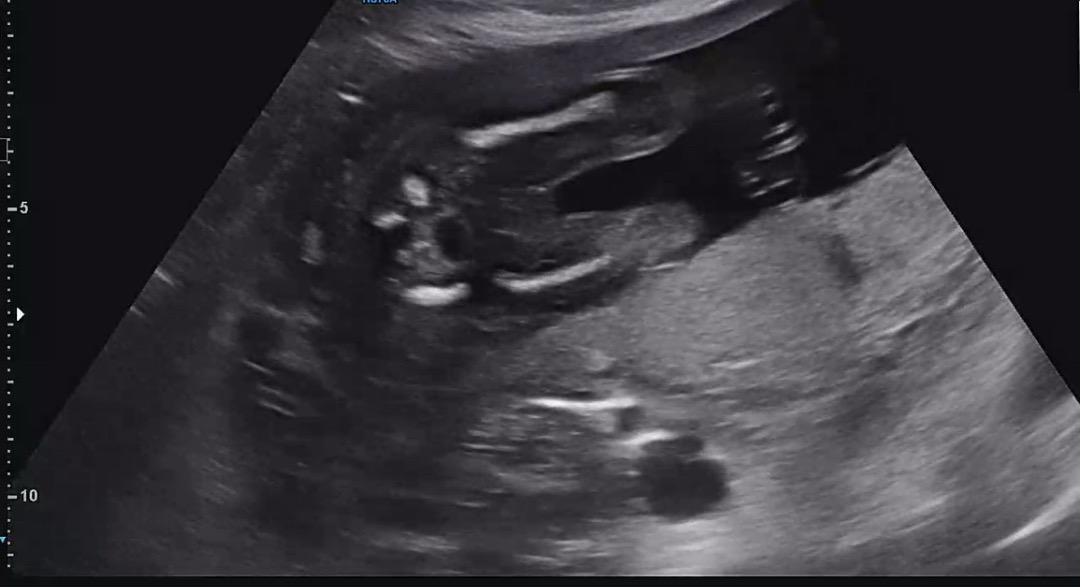

저는 첫째 딸 지금 둘째 아들인거확인했는데 아들은 하얀게 튀어나와야해요. 딸이에요.

지난번에 15-16주쯤 갓을때 아들같다고 하셨는데 오늘 볼때는 아무런 말씀도 안해주시고 제대로 봐주시지도 않으셨네요ㅠㅠ 혹시 아들 맞나요?

완전 딸인데용

아들둘 막내딸인데..이번에 막내초음파랑똑같아 보여요 딸 아닌가요? 아들은 누가봐도 아들이 이더라구요 사진상으로는 매끈해 보여용

다리 사이가 매끈한 느낌이 딸같은걸요??